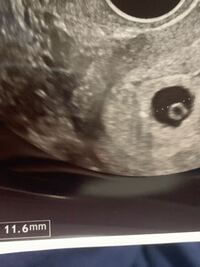

コメントトラックバック                masakohime卵黄卵黄【安心のメーカー直販】3980円以上で送料無料 当社独自のニンニクエキスをプラスした特許商品です。助産師さきの「いいママより、幸せなママになろう!」卵黄嚢が見えた!でも胎嚢は小さい6w6d心拍確認できず…でも卵黄嚢確認!f:id:tio_jobtzp:20160626100644j:image第3回 共食いも胎盤も! サメは「繁殖様式のデパート」ナショナルジオグラフィック日本版サイト画像ママと、小さな宝物♪妊娠3ヶ月 妊娠8週 9週 10週 11週 妊娠初期 の超音波写真 妊娠 出産 育児に関する総合情報サイト ベビカム画像画像f:id:sssebu:20190302010328p:plainきっといつか✧KLC 2人目妊活 胎嚢確認外でのんびり胎嚢25ミリ(胎芽、卵黄嚢なし)画像画像画像Yahoo!知恵袋妊娠7週5日。

胎のう、卵黄嚢のみ確認。胎芽未確認。